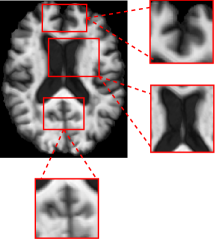

The classification framework is built upon a pretrained 3D U-Net [35]. To adapt the architecture for the task under study, the decoder is dropped, and the encoder serves as a domain-agnostic feature extractor (Fig. 2). The encoder output is then globally average-pooled to produce a compact feature embedding. Finally, a classifier head maps these features to class logits. This forms the basis of the classification model.

Refer to caption

Figure 2: Encoder architecture of 3D U-Net.